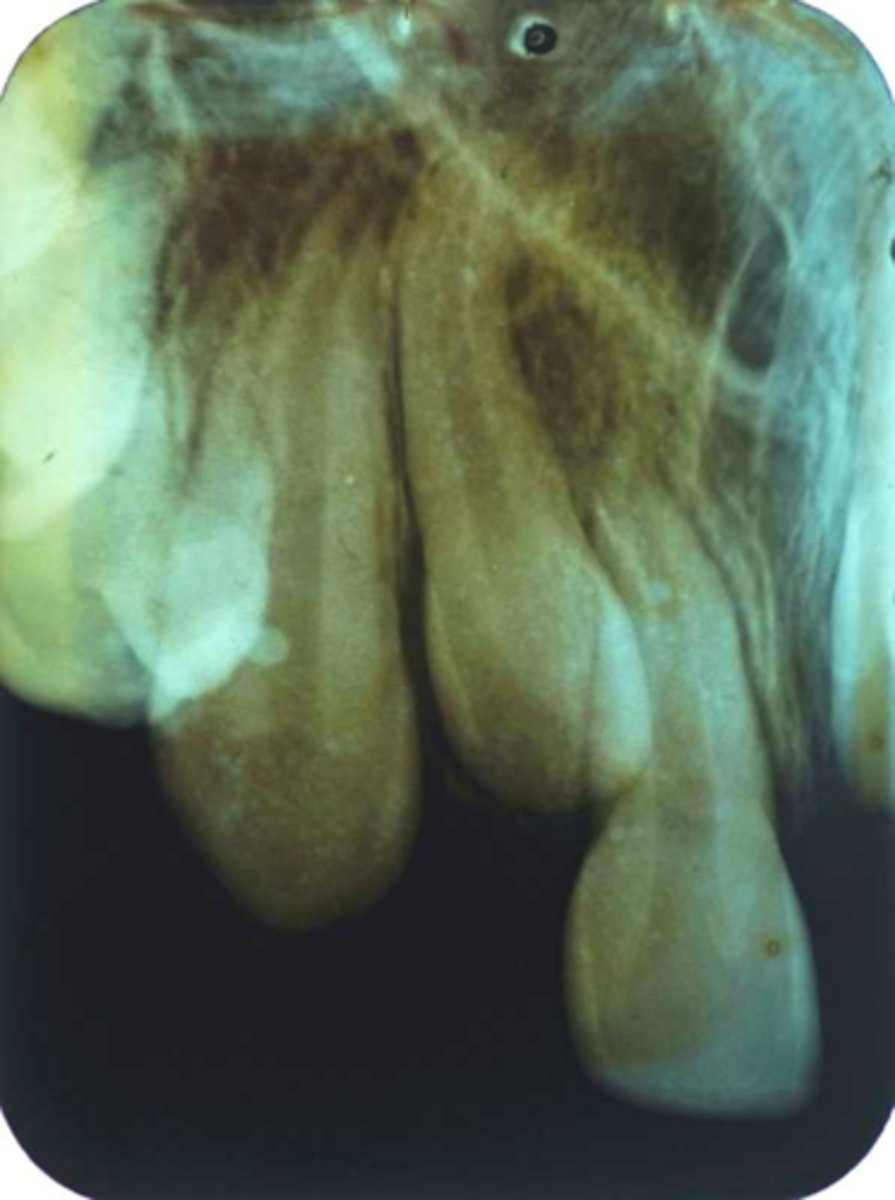

Incorrect Vertical Angulation-->Elongated Images

-Teeth appear long and distorted

-Vertical angulation was insufficient or too flat, resulting in images that are longer then the actual teeth.

-Occurs more often with the bisecting technique

-To prevent use adequate vertical angulation

Tube Head & PID-->Elongation of the Image

-Bisecting technique error

-Insufficient Angulation (not steep enough), causing elongation or increased anatomy of the teeth and cutting off apex.

3. Elongation of the image: Insufficient vertical angulation